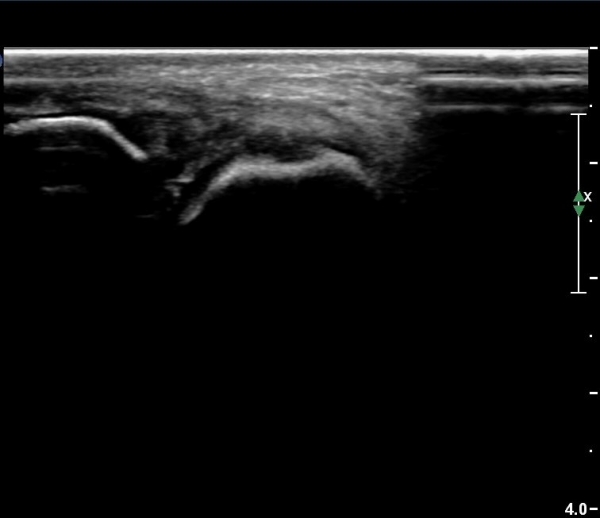

Àü°ÅºñÀδë Á¾´Ü¸é°Ë»ç¿¡¼­  Àú¿¡ÄÚ ºÎÁ¾ÀÌ °¨¼ÒÇϰí ÀδëÀÇ ¿¡ÄÚ°¡ Áõ°¡µÇ¾ú´Ù(»çÁø 2, 3, 4).

Àü°ÅºñÀδë Ⱦ´Ü¸é°Ë»ç¿¡¼­ Àü°Åºñ ÀÎ´ë ¾ÕÂÊ ºÎÀ§ÀÇ °æ¹ÌÇÑ Àú¿¡ÄÚ ºÎÁ¾ÀÌ °üÂûµµ´Ï´Ù(»çÁø 5).